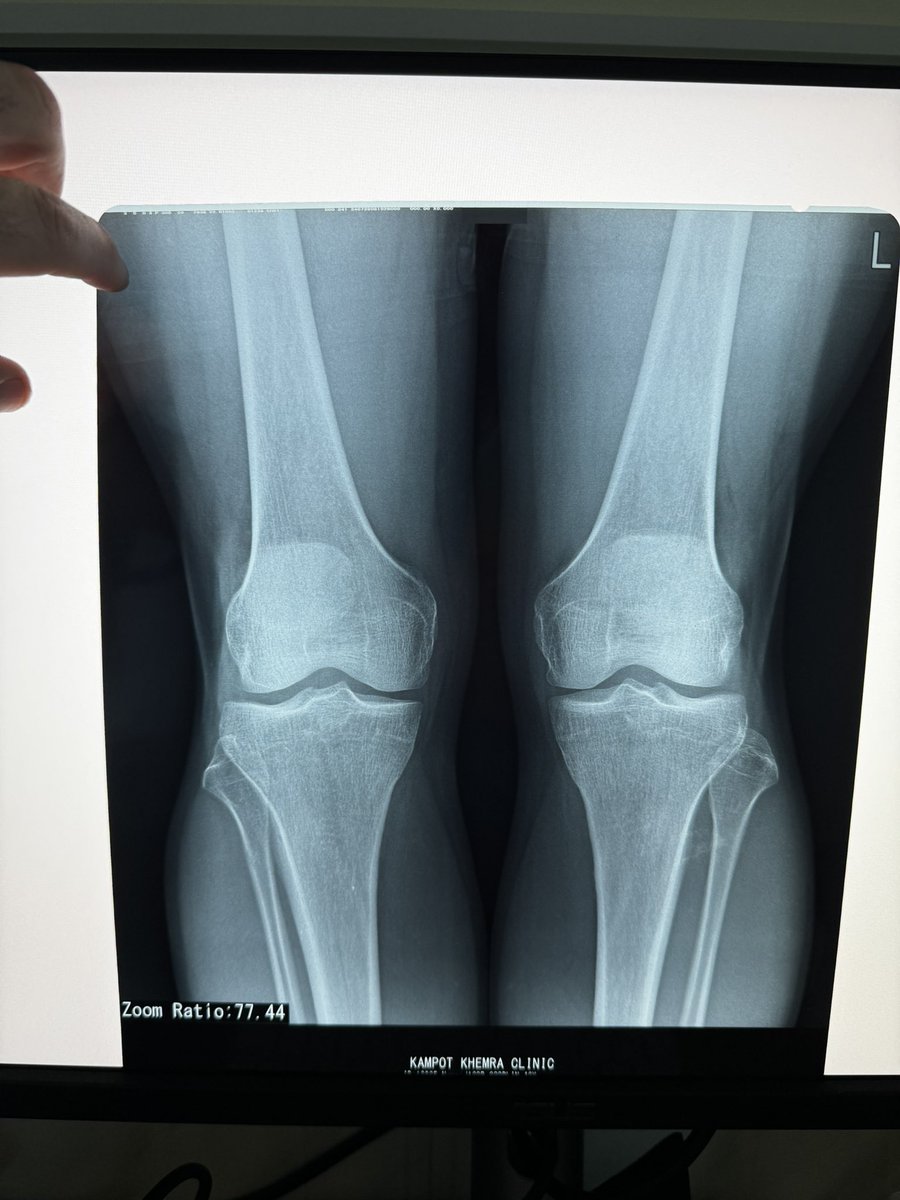

Are there any knee experts out there? It seems there are none in Cambodia. I’ve been experiencing persistent pain in my left knee when walking or running at an angle. While there’s no swelling in the front, there is slight swelling behind the knee. Interestingly, it doesn’t hurt when I run—only when I hit that specific angle while walking or running. I’m concerned about pre-osteoarthritis.